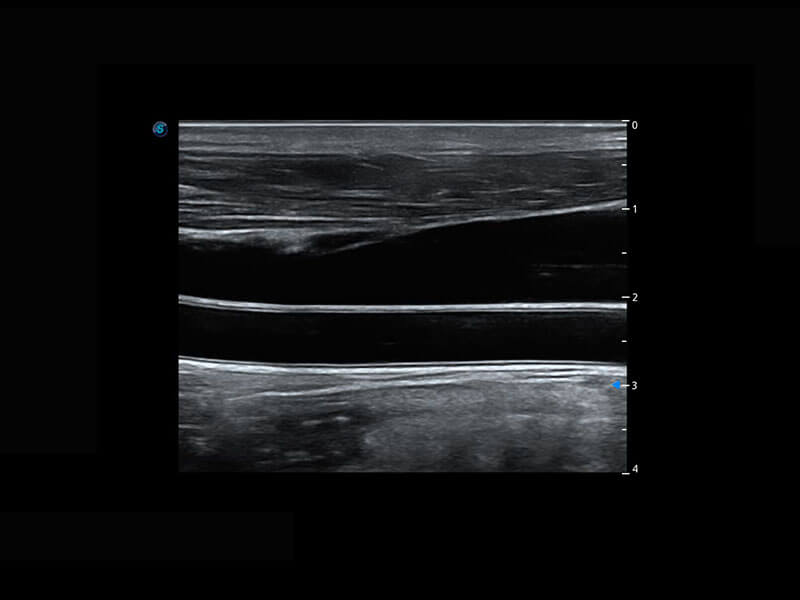

P60搭载宽频带线阵探头、宽景成像、弹性成像技术,为您提供乳腺应用方案。P60支持高频相控阵探头、线阵探头、腹部高频探头、腹部微凸探头等,丰富的探头群搭载敏感的彩色血流成像,适用于新生儿多种脏器检测要求,满足新生儿筛查需求。

新生儿脊髓圆锥